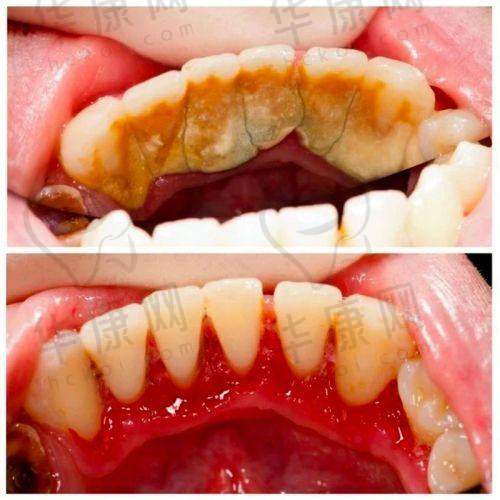

大连米嘉口腔在龈下刮治方面拥有精良的技术。医生采用专精的器械,能够精细地去除牙龈下的牙结石和菌斑。在治疗过程中,运用超声波和精细的手工刮治相结合的方式。超声波可以快速震碎大块的牙结石,而手工刮治则能对一些细小的牙结石和病变组织进行细致清理,确保治疗的完全性。此外,该口腔机构还不断引进新的治疗技术和理念,紧跟口腔医学的发展步伐,为患者提供更优质的治疗成效。